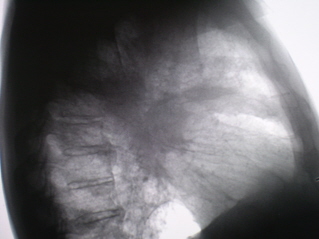

На линейных томограммах, произведенных в боковой проекции (иллюстрации 5, 6, 7, 8, 9) фиксируется картина «инфильтративно измененной легочной ткани». На иллюстрации 7 в 6 сегменте дифференцируются очаги различных размеров, преимущественно малой и средней интенсивности.